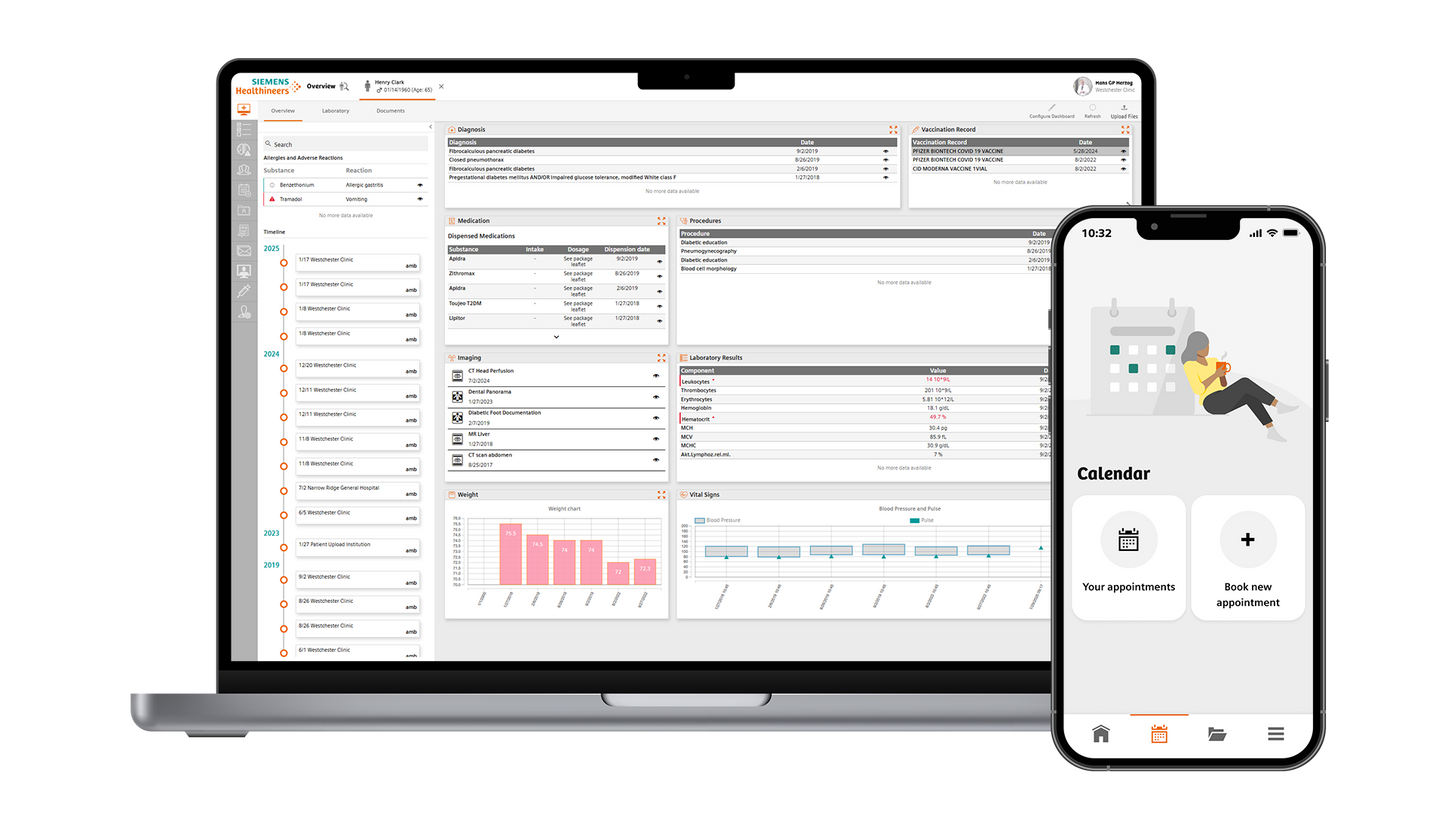

We are empowering decision making for technologists, radiologists, and clinicians along the whole imaging value chain and making it even smarter – allowing healthcare professionals to make the right decision at the right time within the patient pathway. Our AI-powered solutions are not just tools but essential allies in the modern medical imaging landscape, designed to increase productivity, improve clinical precision, and be integrated seamlessly.

By reducing administrative burdens

Use seamlessly integrated intelligence to acquire the best images and accelerate your decision making and reporting process through the smart use of data and AI technology. Explore each step within the smart imaging value chain to learn more about our AI portfolio in radiology.